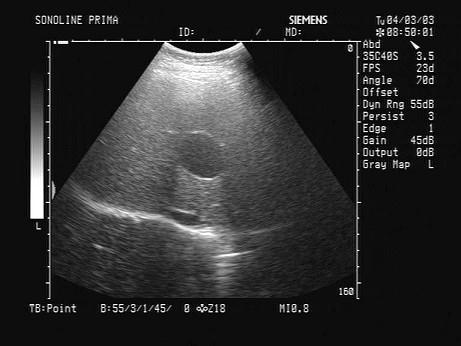

问题 某患者肝脏声像图表现如图,诊断为?(?)

选项 A.肝血管瘤 B.肝癌 C.肝囊肿 D.肝脓肿 E.肝内胆管囊状扩张

答案 C